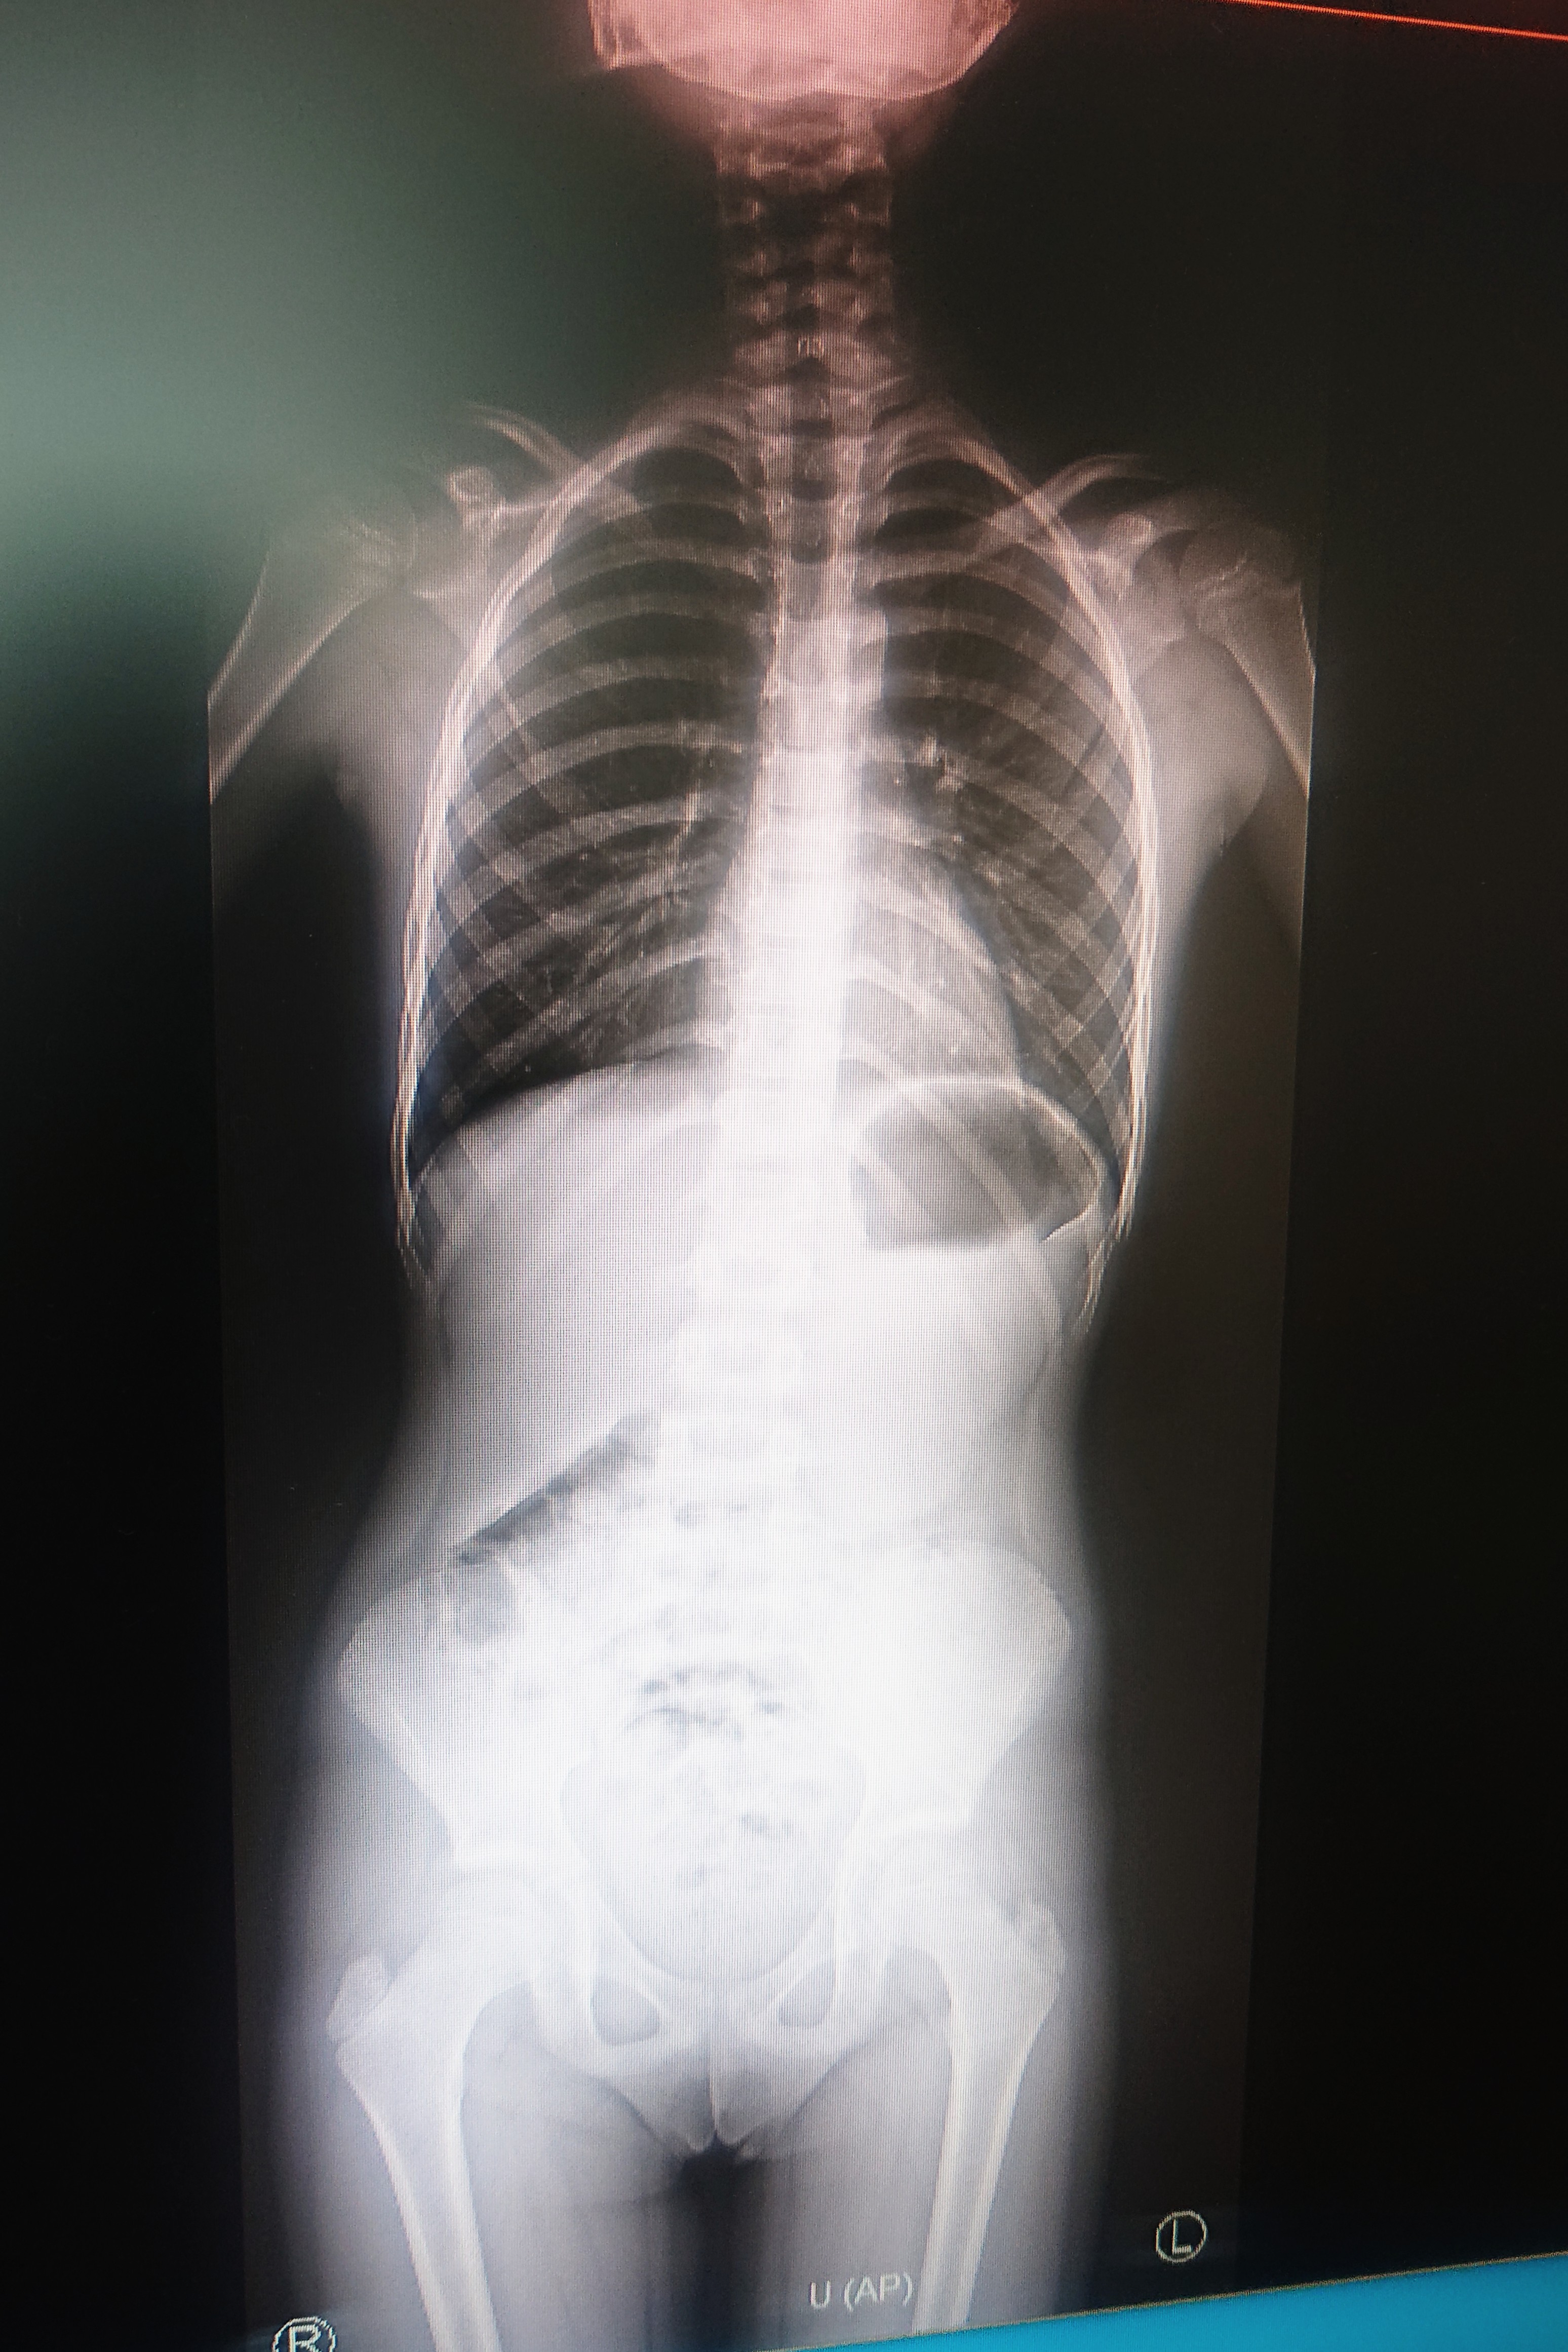

Dobra wiadomość dla osób ze schorzeniami ortopedycznymi i skrzywieniem kręgosłupa „Kleszczowska Przychodnia Salus” może się pochwalić nowym aparatem RTG. Od niedawna rozszerzyliśmy nasza ofertę o tzw. skalometrię (ang. stitching).

Nasi technicy wykonają zdjęcie RTG całych kończyn długich i całego kręgosłupa a następnie uzyskamy obraz diagnostyczny obejmujący razem kilka części anatomicznych połączonych w całość. Dzięki takiemu zdjęciu lekarze będą mieli pełny obraz i dobiorą odpowiednie procedury medyczne.

Skalometrię stosujemy przede wszystkim w diagnostyce schorzeń ortopedycznych, jest bardzo pomocne dla oceny skrzywień kręgosłupa i nieocenione dla fizjoterapeuty.

Co bardzo ważne: czas badania jest bardzo krótki, zaś dawka promieniowana znacznie mniejsza niż w przypadku tradycyjnych aparatów analogowych.